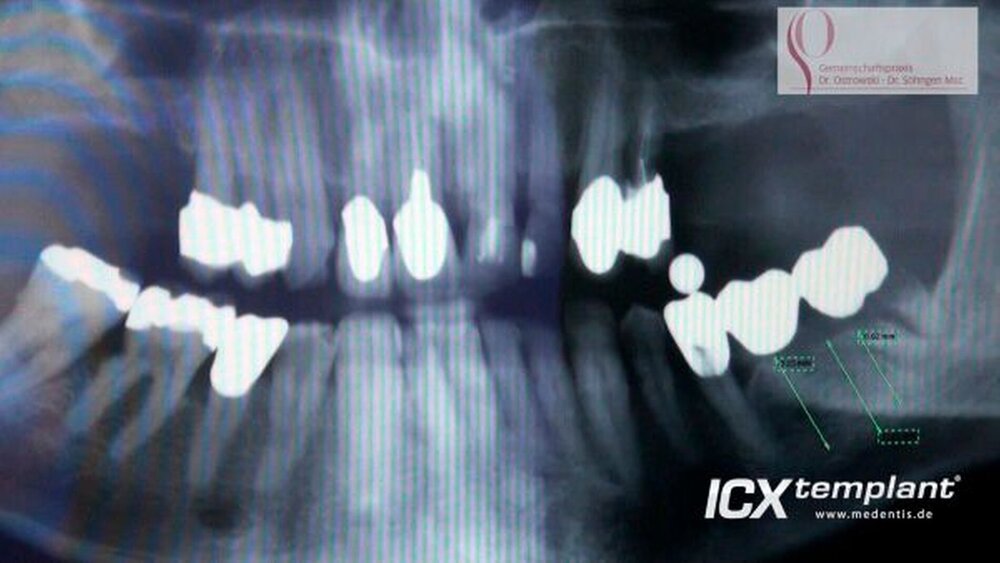

ICX-templants mit Knochenaugmenation und beidseitigem Sinuslift

Sieben ICX-templant Implantate im Ober- und Unterkiefer für eine spätere festsitzende Versorgung mit Knochenaugmentation und beidseitigem Sinuslift.

Dr. Bernd Söhngen Master of Science in Oral Implantology Tätigkeitsschwerpunkt: ImplantologieGemeinschaftspraxis Dr. Ostrowski & Dr. Söhngen Habichhorster Straße 5 31655 Stadthagen